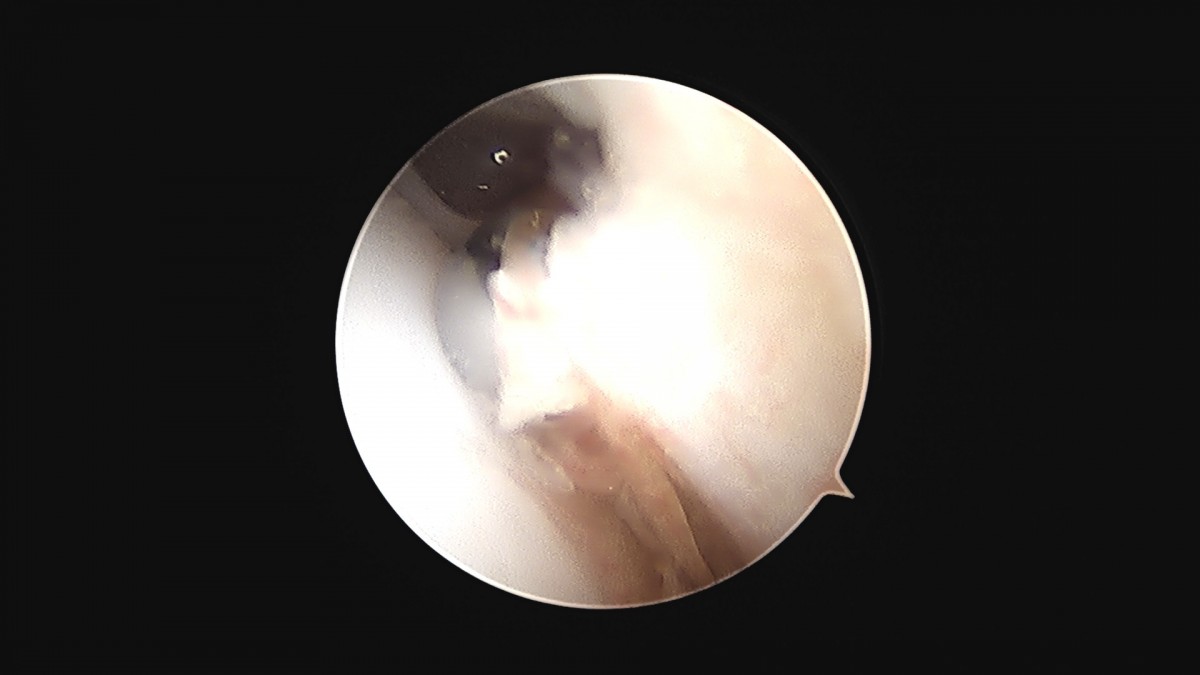

이재상원장님 발목 활액막 절제술 및 인대 봉합술 신진O 환자

dae765e4d9ac96aee867c9d6292d8784_1758003733_017.jpg